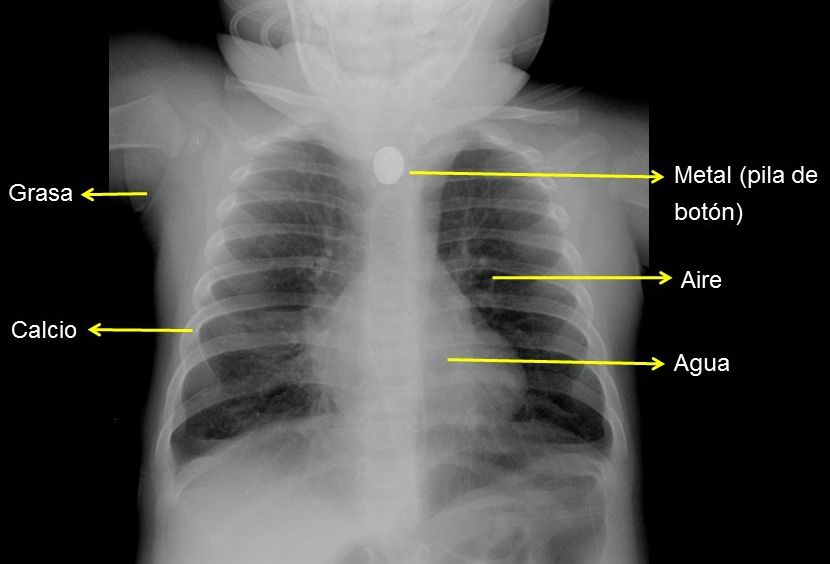

Lactante de 6 meses tras ingesta de pila de botón

Las densidades radiológicas son cinco, de mayor a menor penetración, que podemos identificar en la radiografía de tórax en:

• Aire: parénquima pulmonar.

• Agua: mediastino.

• Grasa: tejido celular subcutáneo.

• Calcio: estructuras óseas.

• Metal: cuerpos extraños metálicos.